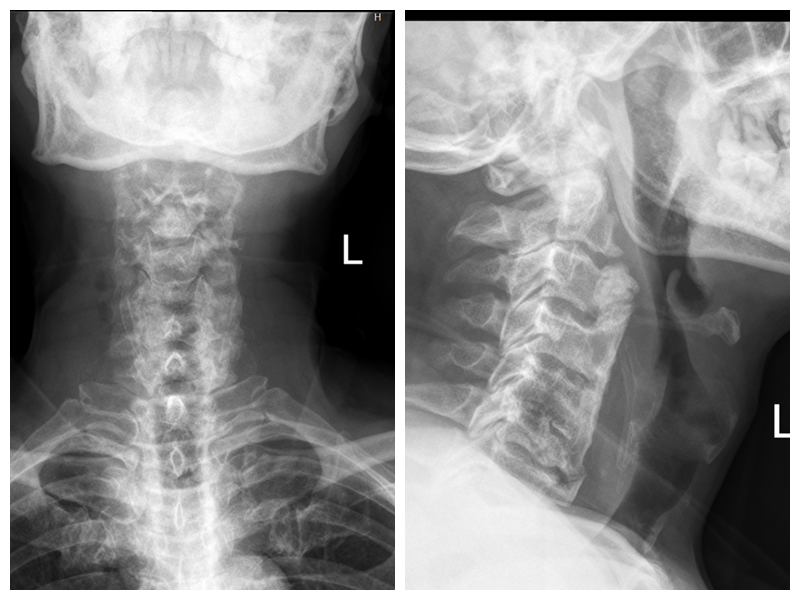

患者术前颈椎影像图

患者术后颈椎影像图

根据患者病情,骨伤七科副主任熊峻带领团队经过术前详细讨论,最终为患者制定出一套最佳手术方案。考虑到患者的主要症状无颈椎脊髓、神经受压症状,经与患者家属充分沟通并取得同意后,团队决定采取经典颈椎前路手术方式,在全麻下行单纯颈椎前路骨赘切除,解除颈椎前方骨赘对食管的压迫。术后患者喝水没有呛咳,进食吞咽困难感明显缓解,患者和家属非常满意术后效果。